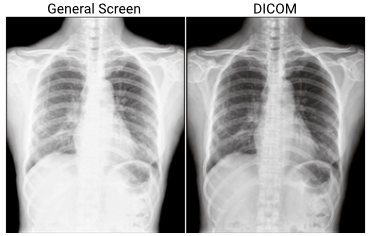

Per garantire, però, che l’occhio umano possa rilevare quante più informazioni possibili, i sistemi di visualizzazione dovrebbero essere impostati su Digital Imaging. In particolare, la parte 14 dello standard DICOM impone la calibrazione del display basandosi sulla curva di risposta della luminanza di Barten, nota anche come curva DICOM. Quest’ultima è ampiamente utilizzata e ha dimostrato di funzionare molto bene per le immagini in scala di grigi, assicurando che tutte le sfumature di grigio vengano visualizzate a distanze uguali per l’occhio umano.

I nostri panel PC medicali Wincomm, certificati EN-60601, hanno la possibilità di integrare un modulo apposito per garantire la conformità del display allo standard di visualizzazione DICOM part 14. In questo modo, potranno essere utilizzati in ambiente ospedaliero, pronto soccorso e stazione di cura, per una rapida e immediata visualizzazione di immagini cliniche.